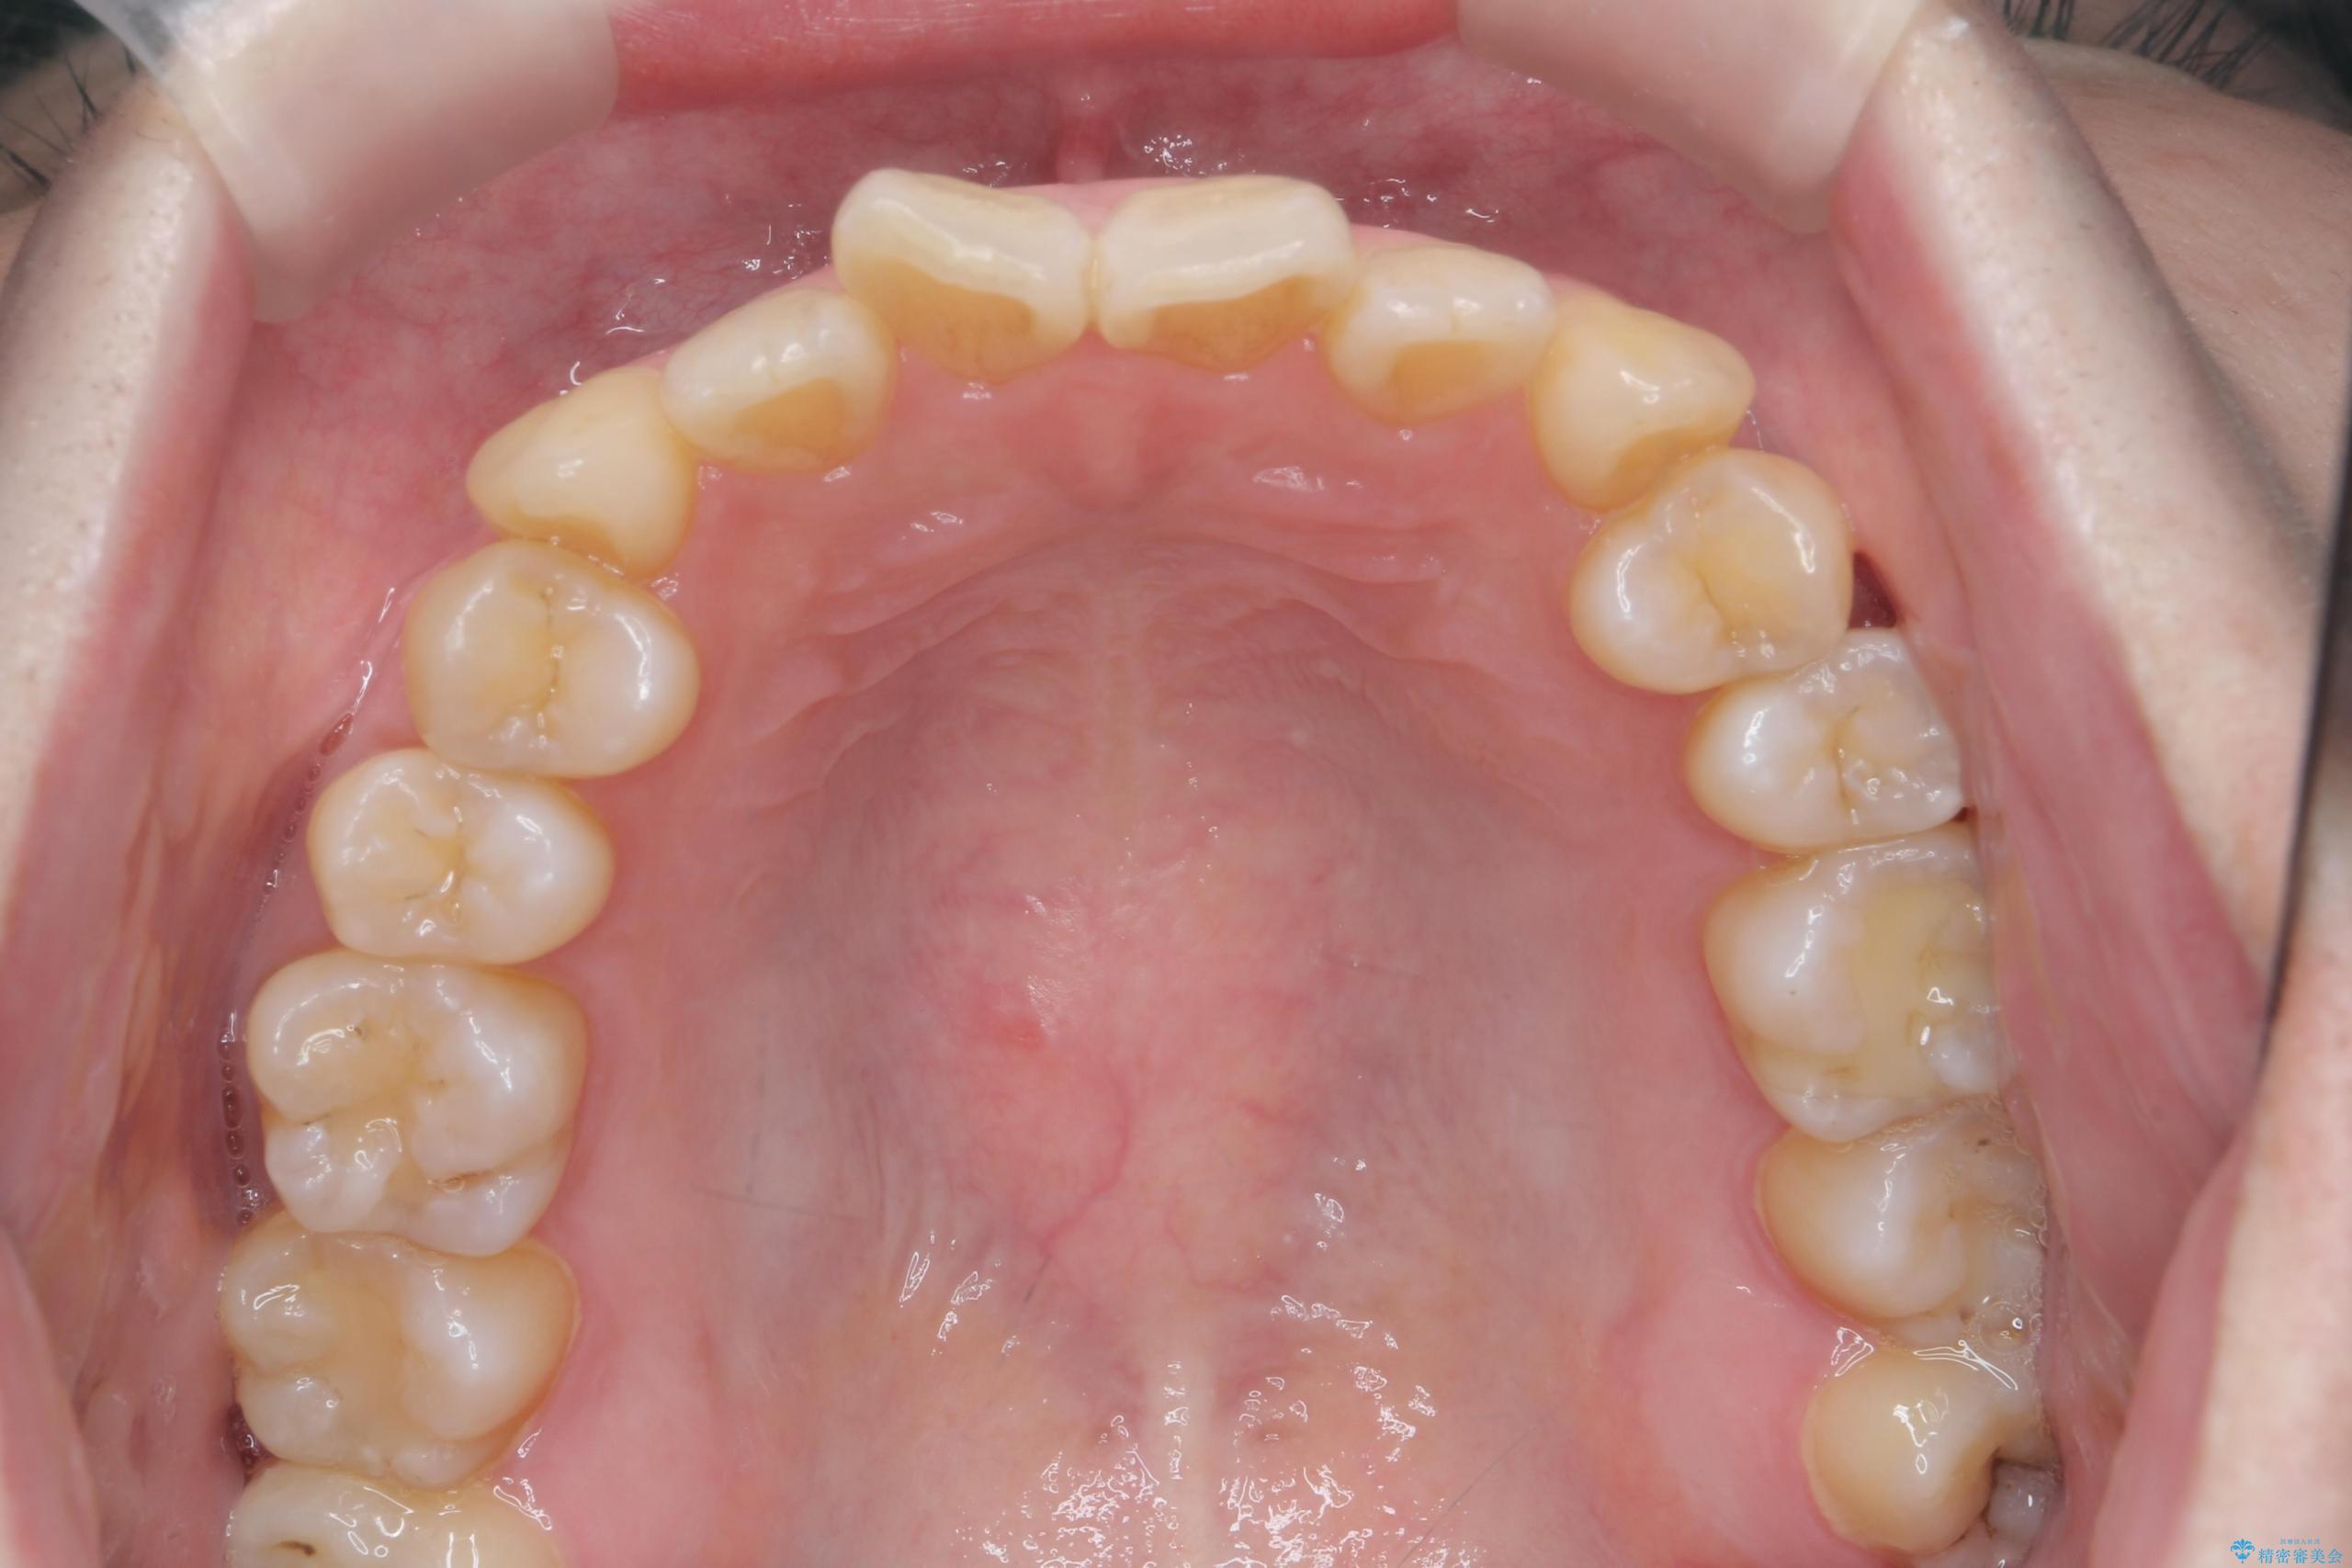

前歯のねじれが気になる、歯並びを改善したいとご来院された患者様です。

歯のねじれをきれいに取るのは、インビザライン(マウスピース矯正)だけでは難しい動きです。そのため、事前に4か月間の部分ワイヤー矯正を行い、治療期間を短くし、より美しい仕上がりを目指す計画です。

前歯が綺麗に並び、大変ご満足いただけました。